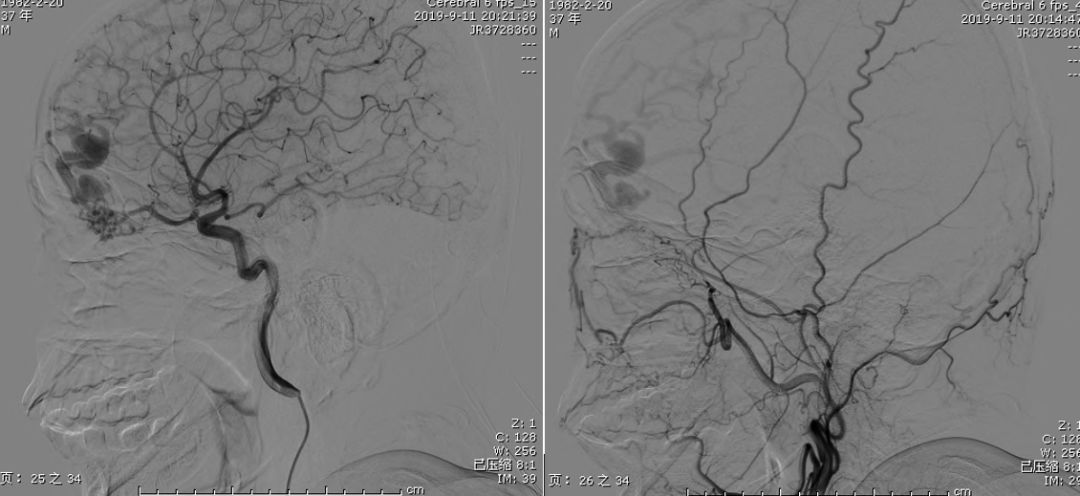

答案:上矢状窦血栓,左额叶静脉性梗死。

患者CT示左侧上矢状窦扩张,左侧颞顶叶小片出血,周围水肿,考虑静脉窦血栓,上矢状窦血栓。DSA见下图: